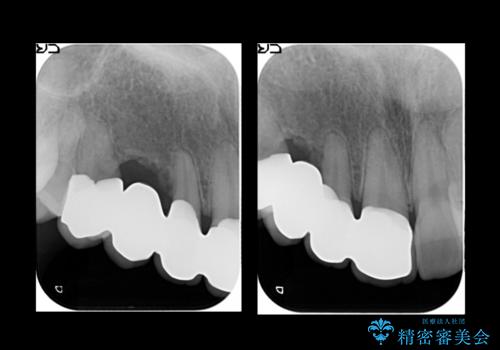

- 右上の歯はもともとなかったが、ブリッジにするのが嫌でプラスチックの歯を応急的に接着剤でつけていたのがとれてしまったとのことでした。

接着剤で留めてある周りが、虫歯になってしまっていました。

しっかり虫歯を取ったうえで、清掃性の高いブリッジにしていくことをおすすめしました。

右上④3②①ブリッジの設計としました。

右上2番単独の支台歯では不足のため、右上12とも支台歯にしています。